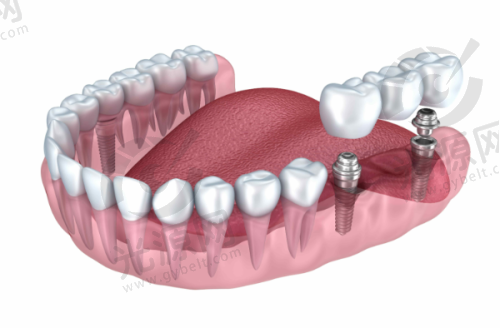

四、唐山地区该项目的技术优势

唐山地区的种植牙技术近年来不断更新,尤其是数字化种植技术和微创种植技术逐渐开始普及。这能有效降低患者的手术风险和修复时间,提高成功几率。